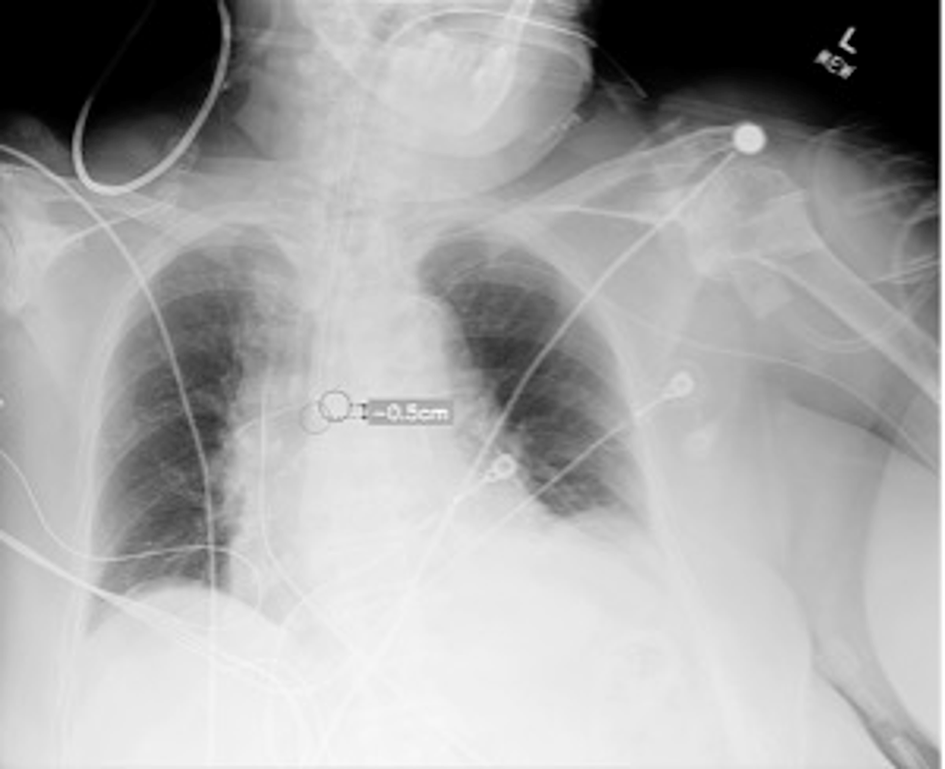

Incorrectly placed endotracheal tubes (ETTs) can lead to serious clinical harm. Studies have demonstrated the potential for artificial intelligence (AI)-led algorithms to detect ETT placement on chest X-Ray (CXR) images, however their effect on clinician accuracy remains unexplored. This study measured the impact of an AI-assisted ETT detection algorithm on the ability of clinical staff to correctly identify ETT misplacement on CXR images.

Four hundred CXRs of intubated adult patients were retrospectively sourced from the John Radcliffe Hospital (Oxford) and two other UK NHS hospitals. Images were de-identified and selected from a range of clinical settings, including the intensive care unit (ICU) and emergency department (ED). Each image was independently reported by a panel of thoracic radiologists, whose consensus classification of ETT placement (correct, too low [distal], or too high [proximal]) served as the reference standard for the study. Correct ETT position was defined as the tip located 3–7 cm above the carina, in line with established guidelines. Eighteen clinical readers of varying seniority from six clinical specialties were recruited across four NHS hospitals. Readers viewed the dataset using an online platform and recorded a blinded classification of ETT position for each image. After a four-week washout period, this was repeated with assistance from an AI-assisted image interpretation tool. Reader accuracy, reported confidence, and timings were measured during each study phase.